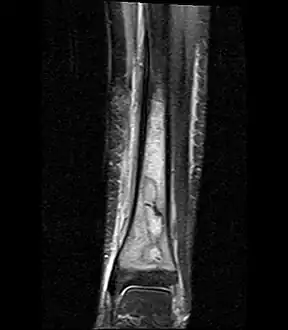

Fat saturated STIR (short tau inversion recovery) image showing hyperintense edema in the calf musculature, marrow edema, and subperiosteal pus. The intramedullary abscess cavity is hyperintense as well. -

Coronal fat suppressed STIR image showing, bone marrow and subcutaneous edema as well as subperiosteal edema. The thin hypointense rim surrounding the intramedullary collection represents the reactive interface between the abscess and the body's attempt to wall it off. -

Sagittal T1-weighted fat-suppressed post gadolinium image showing the extent of the multiloculated intramedullary abscess.